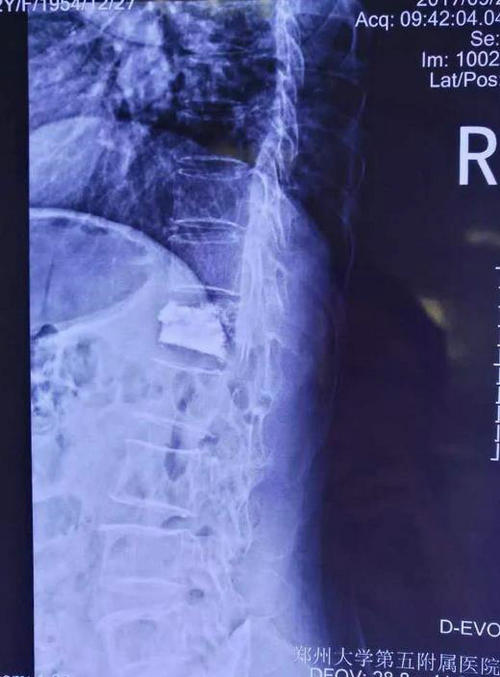

病人病情刻不容缓,应早日治疗,早日为高阿姨解除疼痛,早日出院。当日18点在局麻下,张主任为高阿姨成功实施微创手术,手术仅用时20分钟。术后高阿姨突然发现原来疼痛的部位顿时一点也不痛了。经过综合评估,全科讨论,认为高阿姨完全可以出院,于19点为高阿姨办理了出院手续。

▲ 患者术后正侧位影像